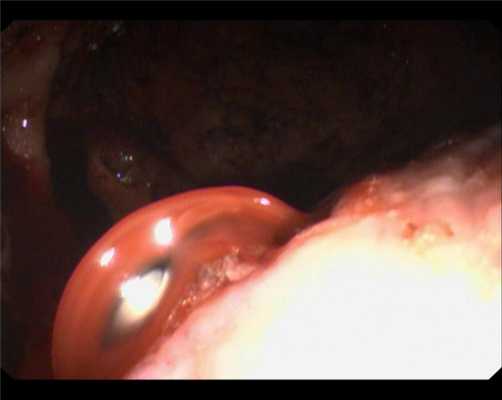

ВРВ пищевода после эпизода кровотечения. Тромбированная вена - тромб белого цвета..